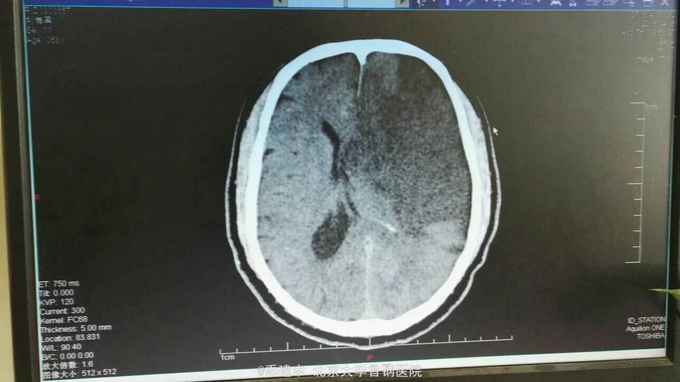

诊断:脑梗死 高血压3级 极高危 2型糖尿病 高脂血症 治疗:入院后给予抗血小板聚集、改善脑供血、清除自由基、扩容,脱水及对症支持治疗。2016.4.16接班后查房发现患者呼之无应答。查体:T:37.7℃;P:95次/分;R:20次/分;BP:202/90mmHg。 深度嗜睡至浅昏迷,呼吸节律尚规整,查体不合作。双侧眼球居中,双侧瞳孔不等大,左侧直径3.0mm,右侧直径约1mm。右侧鼻唇沟浅。双侧Babinski'sign、双侧Chaddock'sign(+)。右侧肢体无自主活动。双肺未闻及干湿啰音,心率95次/分,律齐,双下肢无浮肿。急诊复查头CT示:多发脑梗死,左侧额颞顶叶大面积梗死,建议MRI检查进一步明确。阅片可见侧脑室受压明显,中线移位,有脑疝形成。请神经外科急会诊,建议行去骨瓣减压术。告知患者家属上述情况,家属同意转神经外科行急诊去骨瓣减压术。